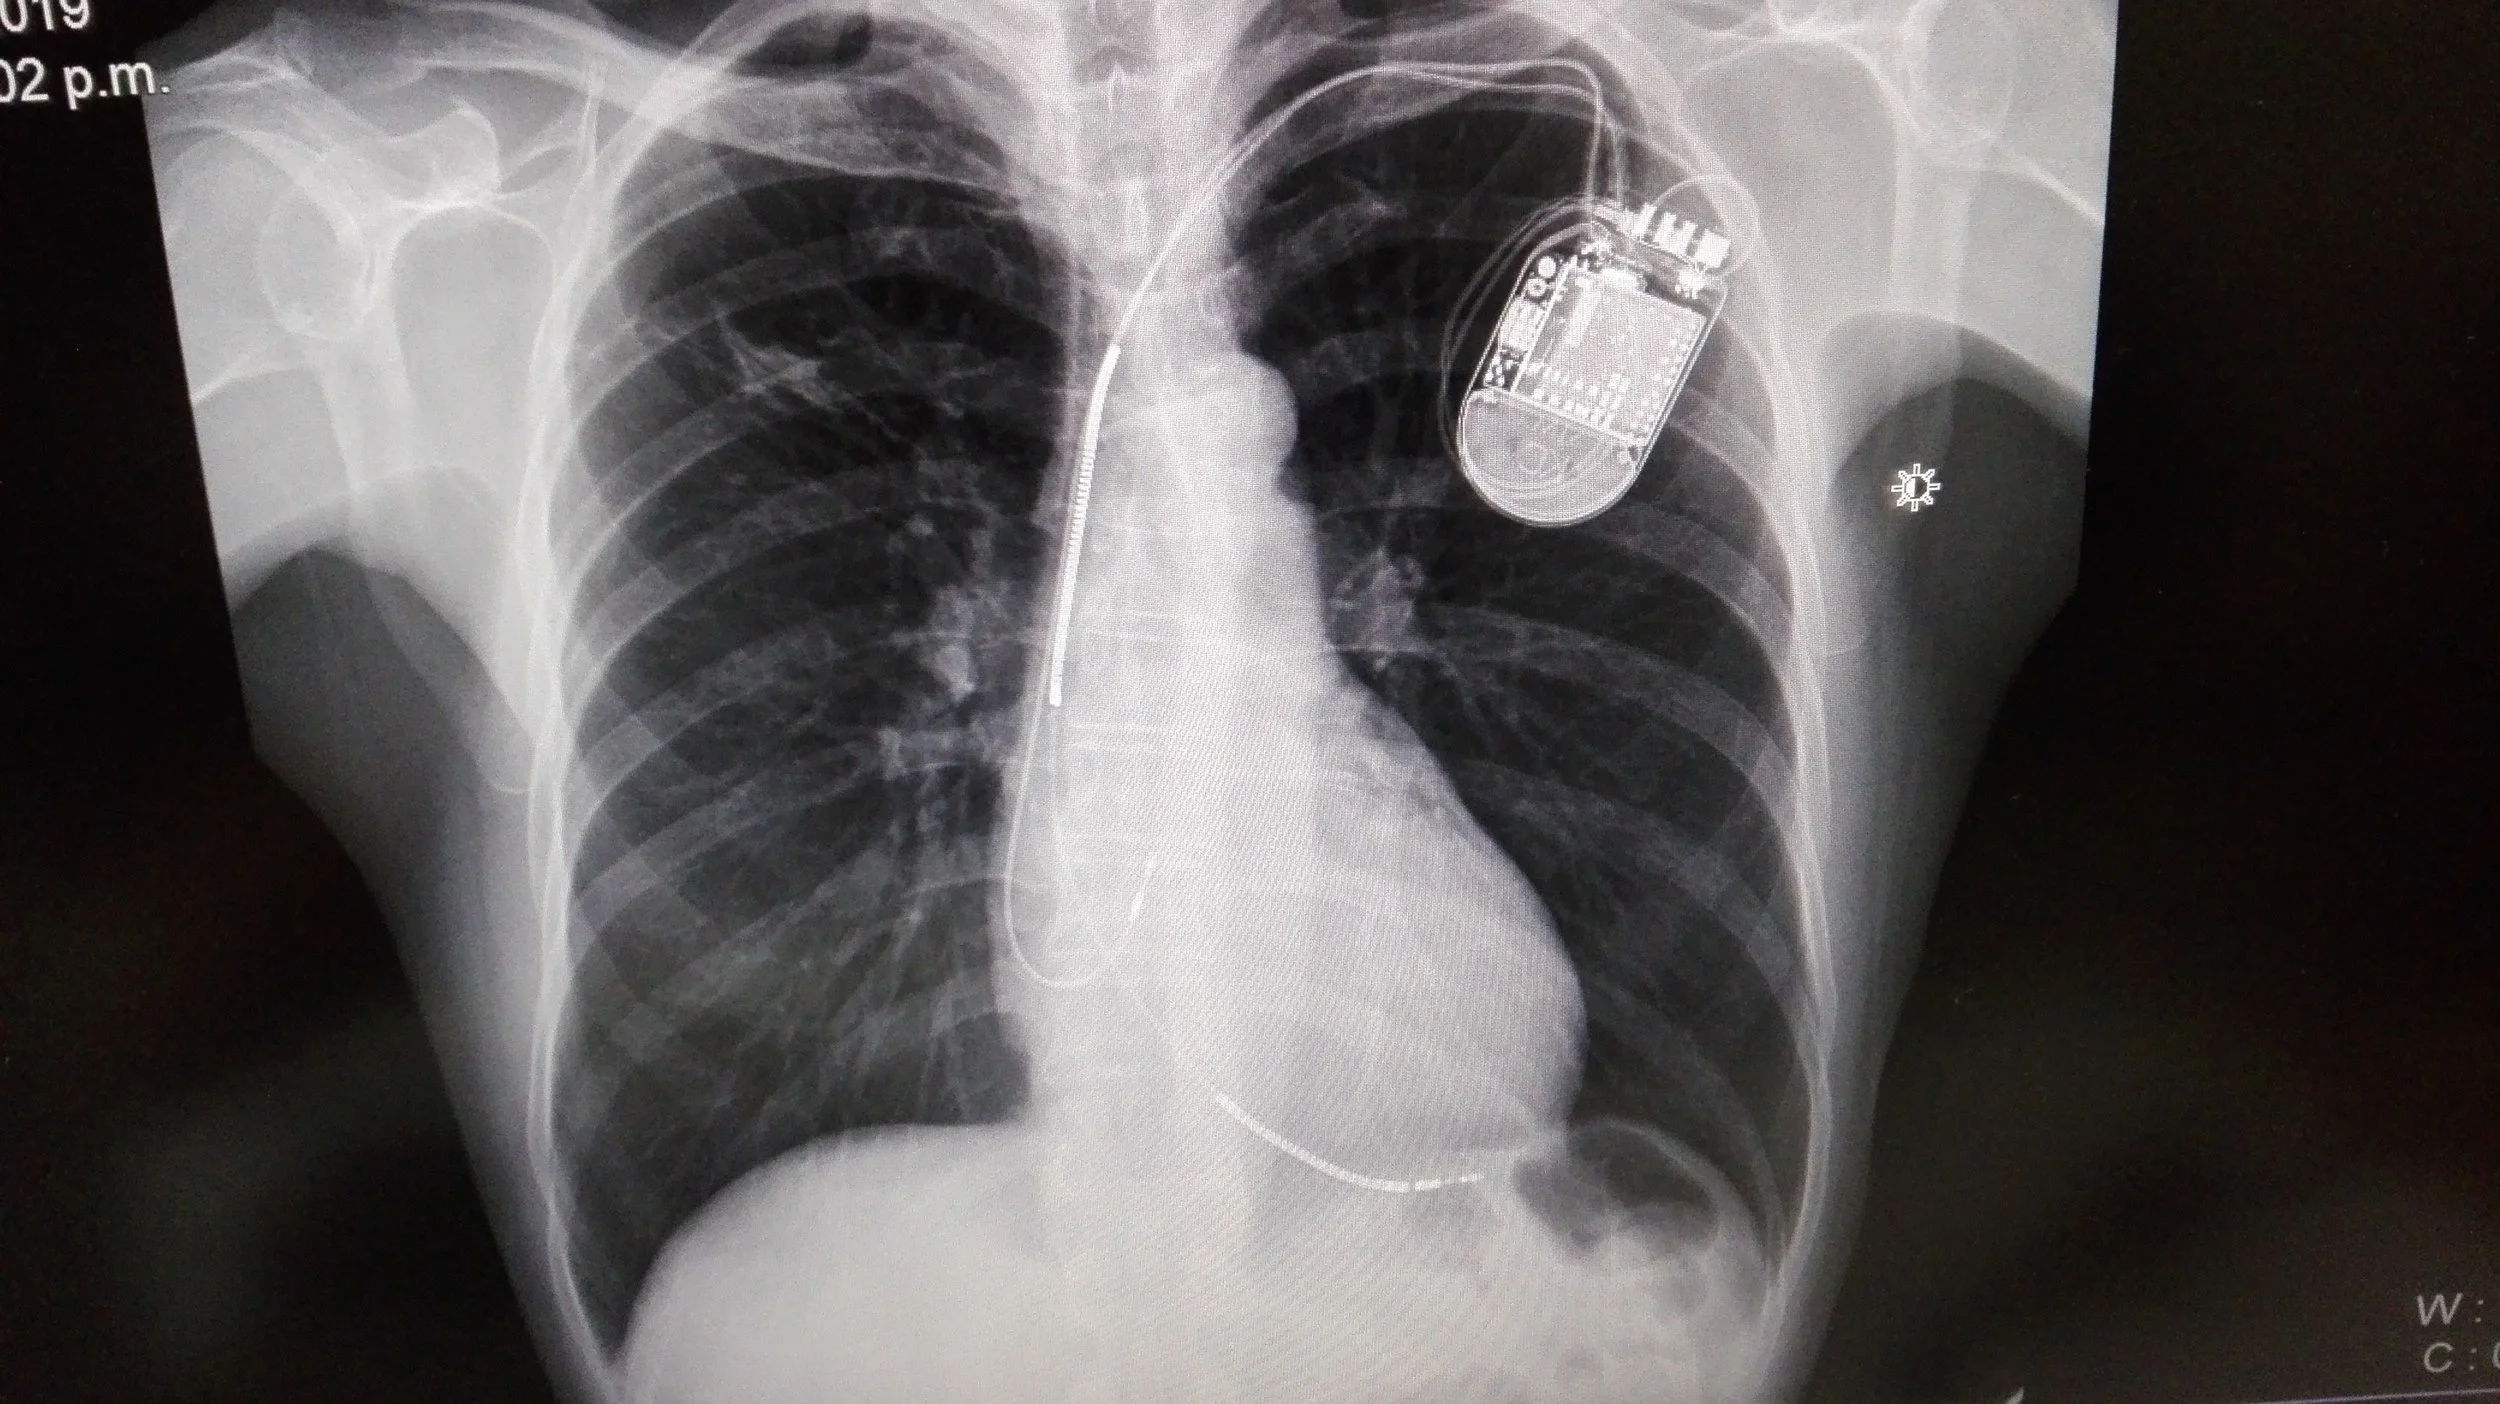

⚡🫀 Clínica de Marcapasos

Seguimiento especializado para revisar, ajustar y asegurar el óptimo funcionamiento de:

• Marcapasos

• Desfibribilador (DAI)

• Resincronizador

En niños, adolescentes y adultos garantizando seguridad y confianza